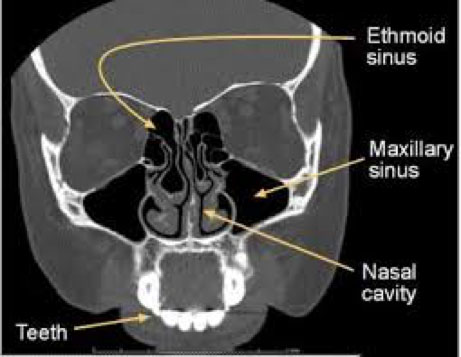

Sinus CT Scan: a low dose, cone beam CT scanner used to provide additional diagnostic information in patients suffering from sinusitis, nasal polyps and facial pain.